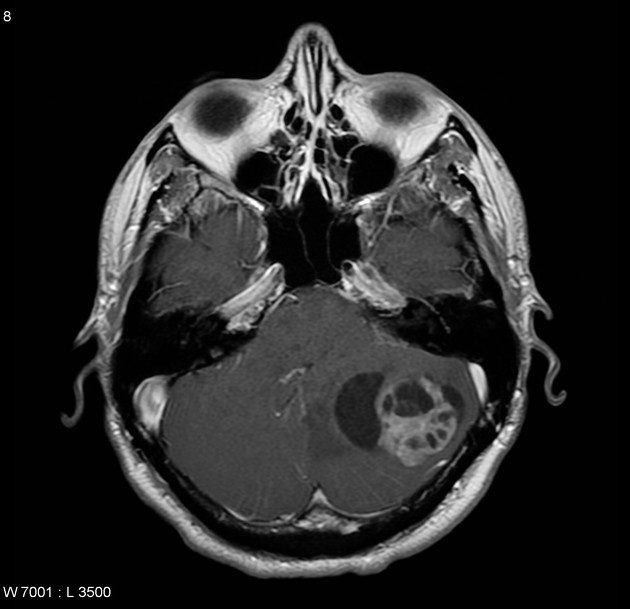

Medulloblastomas

Medulloblastomas are common tumors in childhood, often presenting with vomiting and headache. These tumors are located in midline of the cerebellum (back of the head). Diagnosis is made with MRI, and complete excision can be done safely in majority of the children.